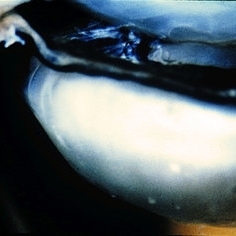

Slide 12-5

Feb 27 2019 by Lancaster Course in Ophthalmology

Congenital glaucoma. Deep glaucoma cup of the optic disk is shown macroscopically in an eye from a 7-year-old with congenital glaucoma.

Condition/keywords: congenital glaucoma